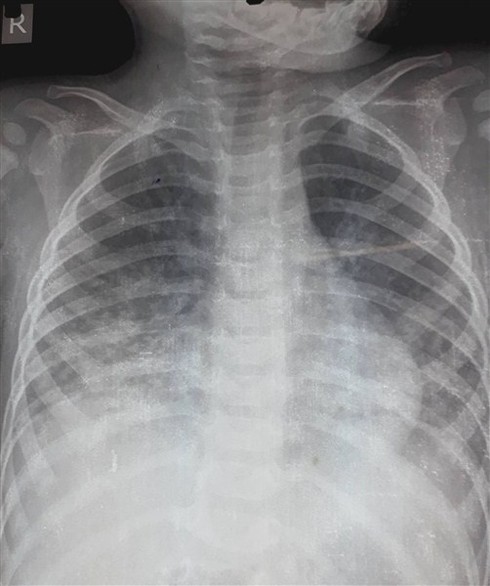

Hình ảnh Xquang của bé Đ. phổi bị viêm nặng |

Tại Bệnh viện Đa khoa tỉnh, qua thăm khám, chụp Xquang phổi, xét nghiệm máu, cháu được chẩn đoán viêm phổi nặng do hít dầu hỏa. Ngay sau đó, cháu được xử trí thở ô xi, kháng sinh, chống viêm.